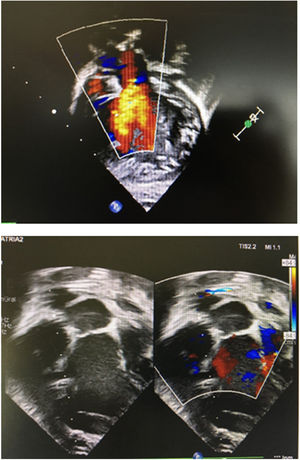

Paciente 2Nuestro segundo caso se trataba de una niña con ventrículo único, discordancia ventriculoarterial, comunicación interventricular, hipoplasia de arco aórtico y estenosis subaórtica. En periodo neonatal se realizó un switch paliativo9 más cerclaje de tronco neopulmonar, con buen resultado. Una dilatación progresiva del anillo neoaórtico produjo una regurgitación valvular hasta convertirse en moderada-severa, a pesar de velos normales. La alternativa de una cirugía tipo David o Yacoub fue descartada, por el pequeño tamaño. Con 6 meses fue reintervenida, desmontando el cerclaje y Lecompte previos para acceder a la neorraíz aórtica10. El diámetro era de 15mm y las dimensiones del rectángulo para la confección del cilindro de 15×67mm. El resultado inmediato fue satisfactorio, con regurgitación central trivial (fig. 4). Lamentablemente, falleció 6 meses después por una sepsis de origen respiratorio, en espera del segundo tiempo para la reparación univentricular.

Paciente 3Finalmente, el tercer caso, un niño, nació con una atresia valvular aórtica, hipoplasia de aorta y arco, además de válvula pulmonar displásica (gradiente 60mmHg). Se daba la circunstancia de que dicha válvula pulmonar actuaba como sistémica, dando flujo anterógrado a la aorta descendente y retrógrado a los troncos supraaórticos y las coronarias. Con 13 días y 3,1kg fue intervenido, realizándose un procedimiento híbrido: cerclaje de ambas ramas pulmonares más implantación de stent ductal, además de neoválvula en posición pulmonar. Para ello, la arteria pulmonar fue seccionada inmediatamente por debajo de la bifurcación. Una de las comisuras fue abierta longitudinalmente hasta el triángulo subcomisural, dadas sus dimensiones reducidas (11mm). El cilindro se realizó a partir de un rectángulo con medidas de 11×50mm. La ecografía inicial mostraba una insuficiencia ligera paracomisural, coincidente con la apertura longitudinal previa (fig. 5). Habiendo descartado la opción de una reparación biventricular compleja (Norwood-Rastelli o técnica de Yasui) que dejase nuestra neoválvula en posición sistémica, fue trasplantado 2 meses después. Un año más tarde, se encuentra en buen estado.